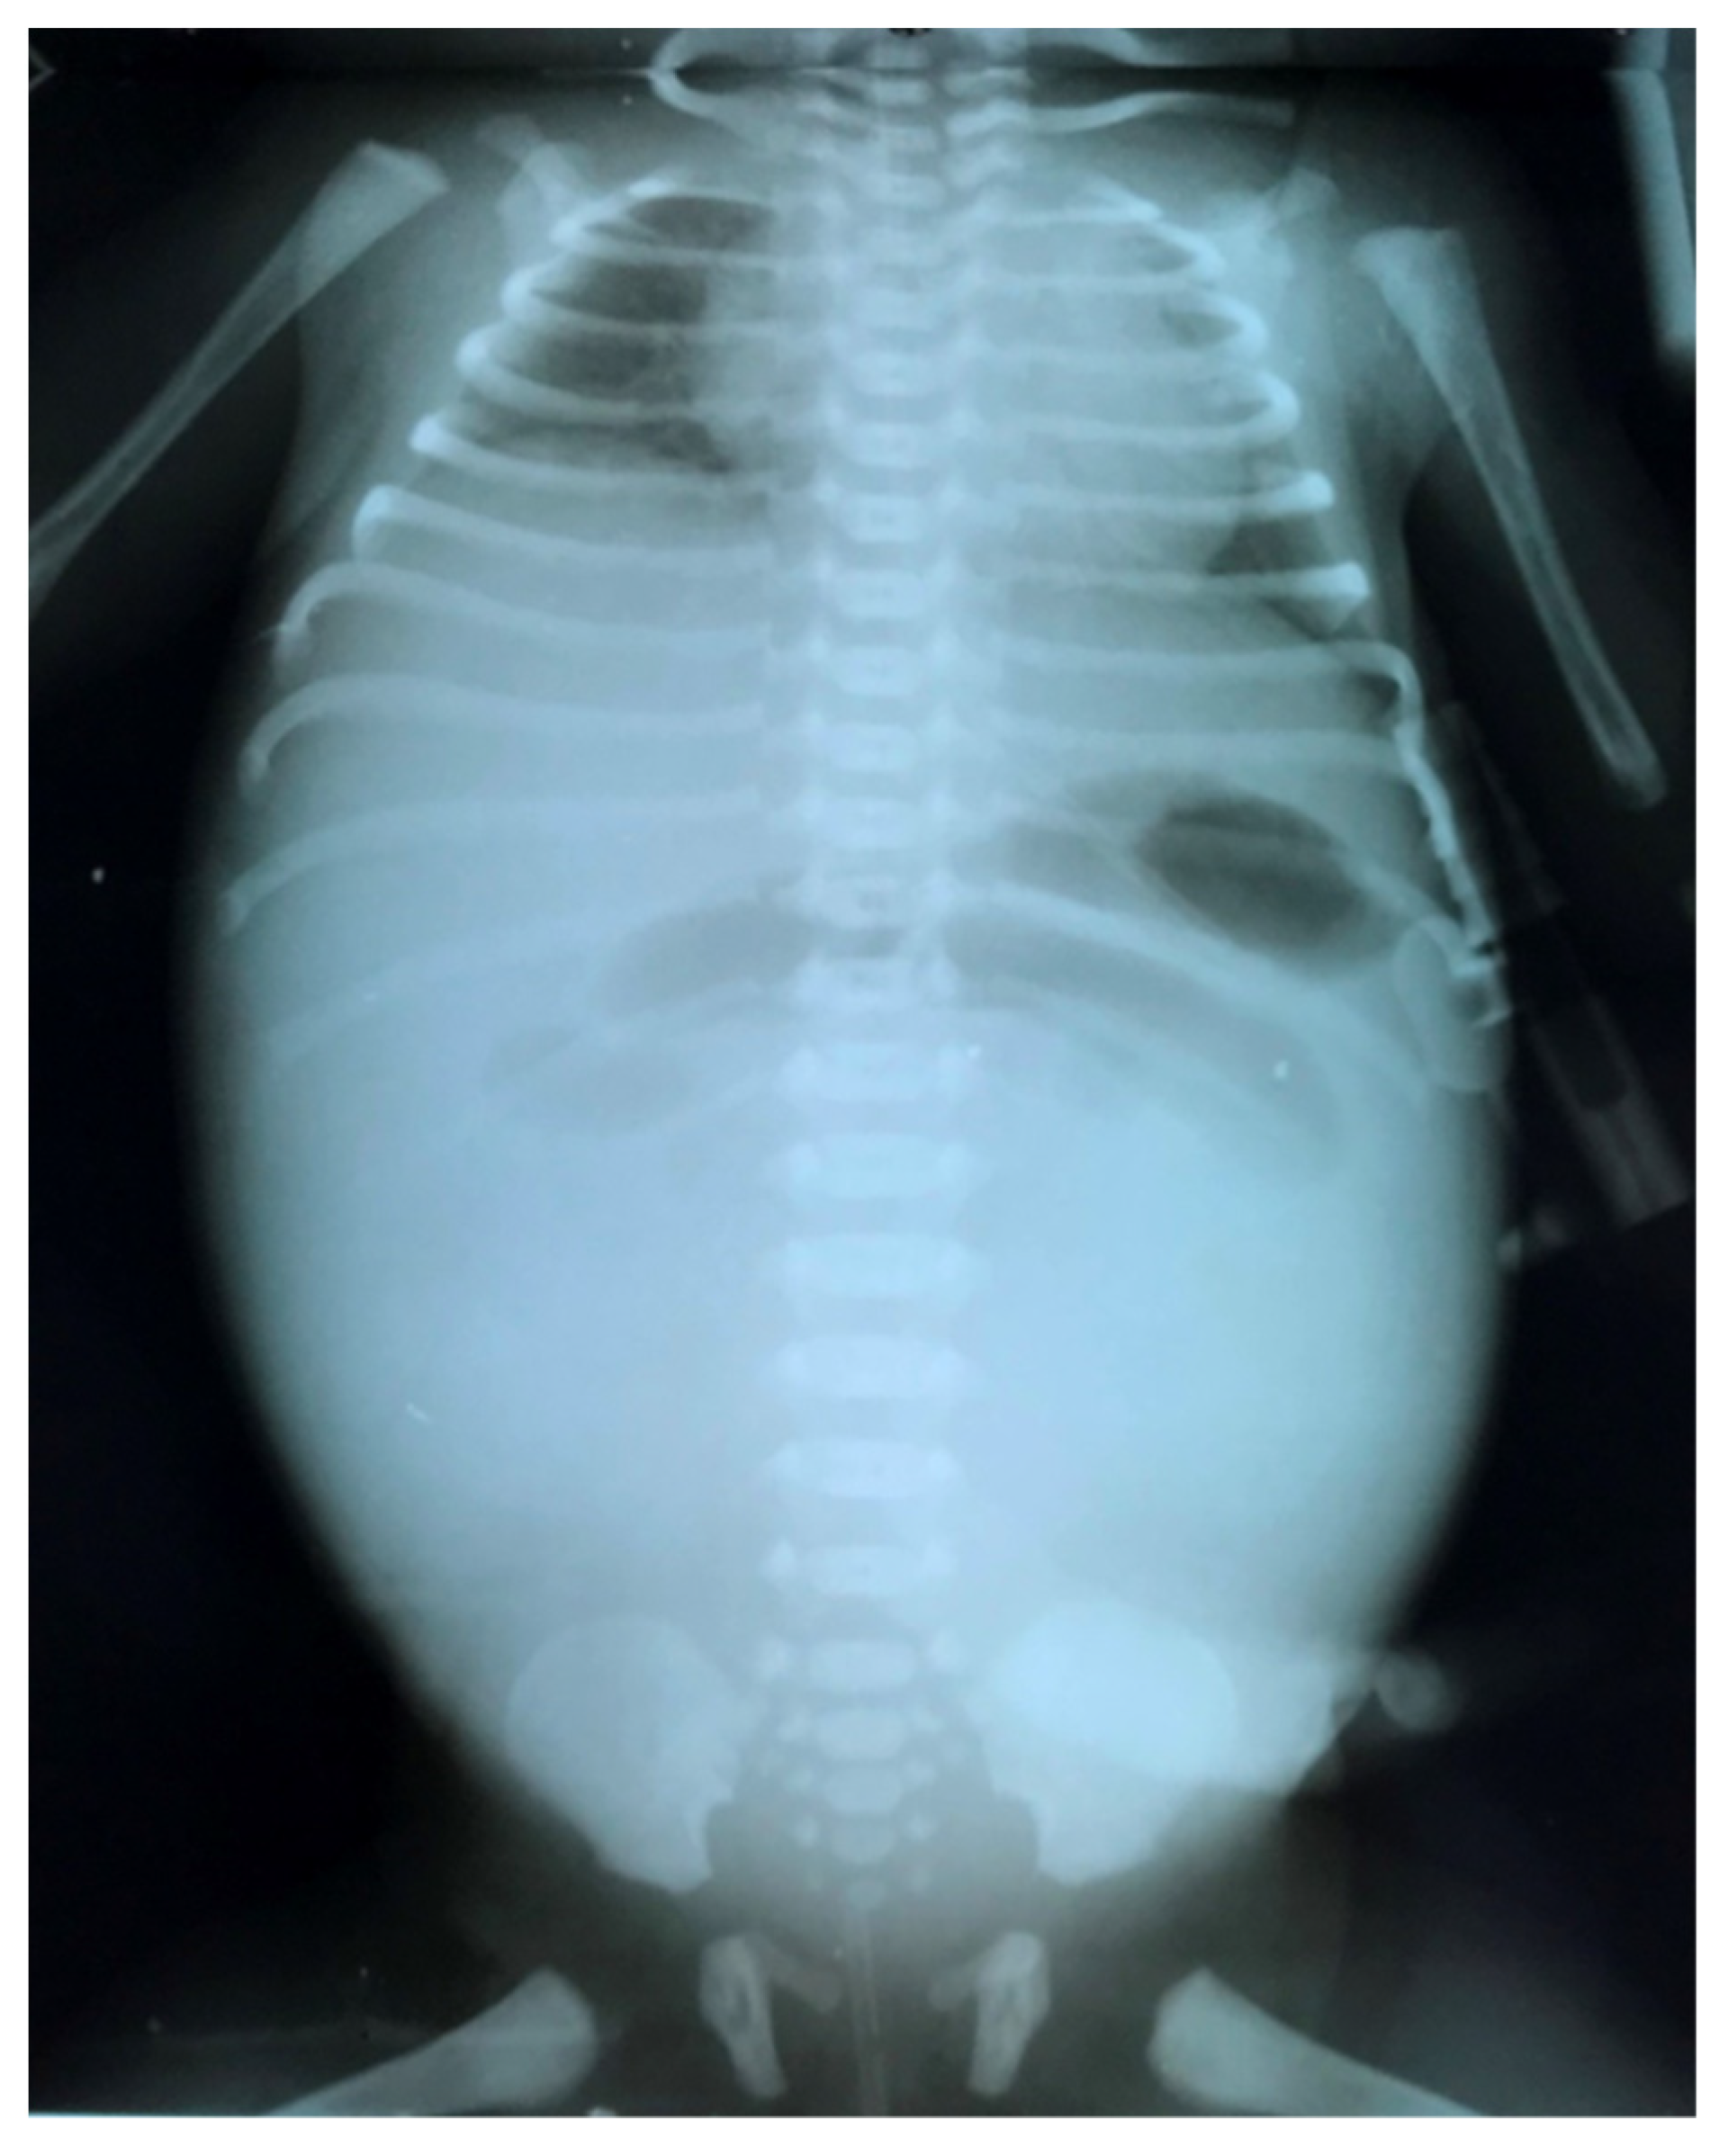

The clinical presentation is usually more spectacular than in the case of simple MI, with bilious vomiting, marked abdominal distension, abdominal wall edema, fever (Figure 6). Respiratory distress may also be caused by substantial abdominal distention. If the neonate is stable, a diagnostic contrast enema can help identify malrotation by pinpointing the cecum’s location and identify a microcolon caused by proximal obstruction in the terminal ileum. If the patient’s clinical condition is deteriorated, a simple abdominal X-ray (Figure 7) and an ultrasound are sufficient to guide operative management. Anyway, infants with complicated MI will always require surgery [8].

Figure 7.

Abdominal X-ray showing dilated intestinal loops in the upper part of the abdomen and opacity due to meconium cyst in the rest of the abdomen.